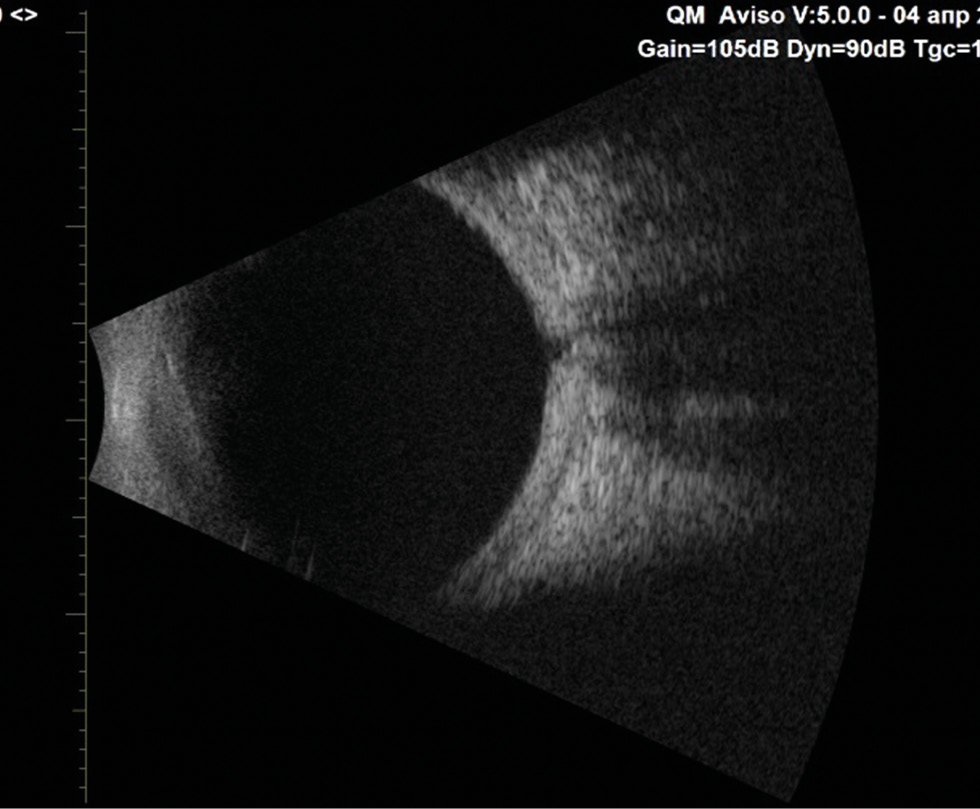

RESULTS: This article presents the clinical case of postoperative choroidal detachment in a child with Sturge–Weber–Crabbe syndrome after microinvasive non-penetrating glaucoma surgery. Against the background of the existing anomalies in the development of an optic disc after antiglaucomatous intervention for decompensated glaucoma, after the normalization of IOP, the patient developed choroid detachment with exudative retinal detachment the next day of operation. After conservative therapy involving bed rest and double instillation of mydriatics for 1 month, the situation was completely resolved and his vision was restored to 1.0.

DISCUSSION: The atypicality of our clinical case of CD lies in the overly pronounced exudative component. In addition to the classic CD vesicles, we observed high exudative retinal detachment as well as high retinoschisis, which is extremely atypical for classical CD. Considering the characteristics of congenital syndrome, it is necessary to accurately differentiate atypical CCA from the rare choroidal effusion syndrome, which also includes CCA with retinal detachment, but does not present with retinoschisis. Against the background of conservative therapy with bed rest and two instillations of mydriatics for 1 month, the situation was completely resolved, and the patient’s vision was restored to 1.0. In the treatment of such patients, it is always necessary to consider their individual anatomical features as well as to understand the detailed pathogenesis of the complications that arise before rushing to repeat surgery.